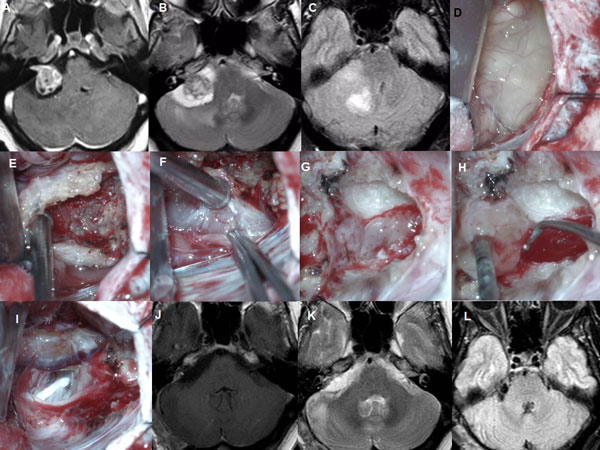

Figura 2: Paciente masculino de 59 años, operado de SV T1 izquierdo. A-C: RM preoperatoria. D-I: hallazgos intraoperatorios. J-L: RM postoperatoria.